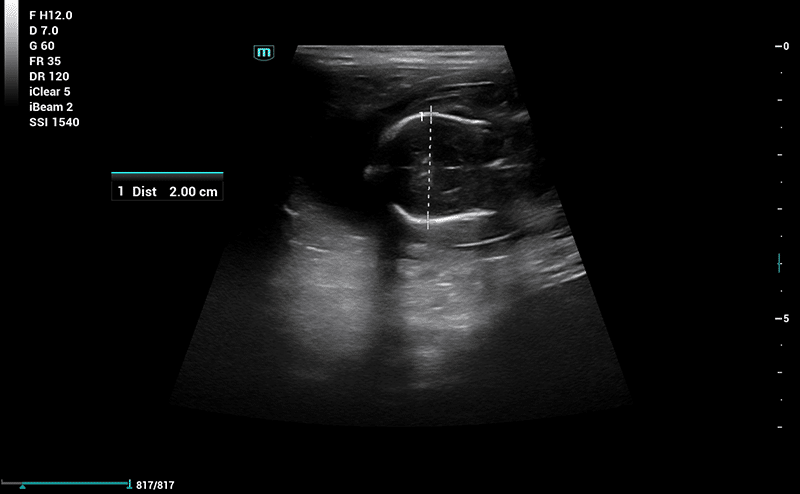

Drægtighedsscanning

Drægtighedsscanning anbefales omkring dag 24-26. Her vil vi dels kunne konstatere drægtighed, men også kigge på fostrenes udviklingstrin og hjerteslag, samt komme med et estimat på antal fostre.​

Måling af længde på foster i forbindelse med drægtighedsscanning.